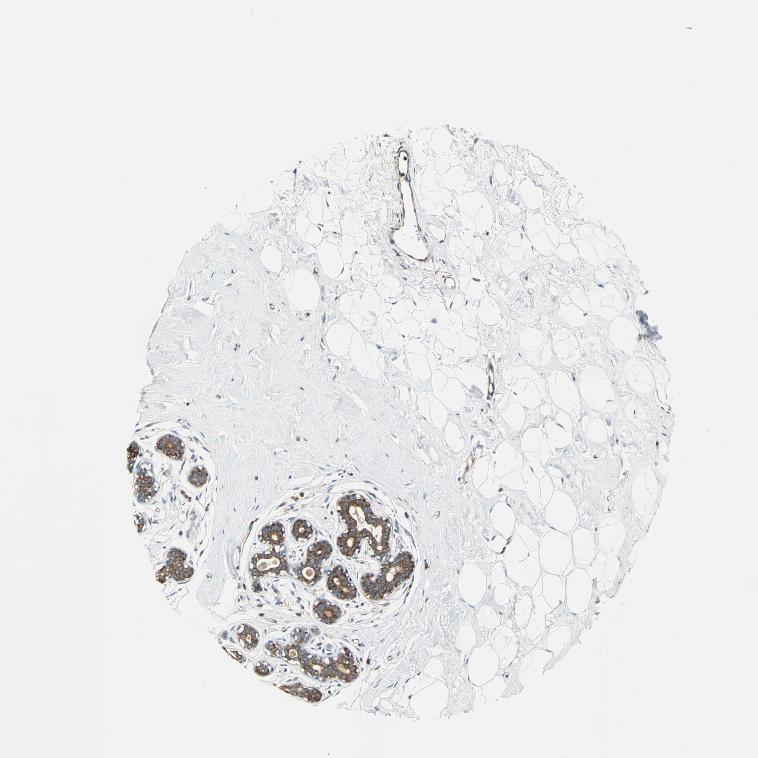

BREAST - Antibody stainingi

Antibody staining in the annotated cell types in the current human tissue is reported as not detected, low, medium, or high, based on conventional immunohistochemistry profiling in selected tissues. This score is based on the combination of the staining intensity and fraction of stained cells.

Each image is clickable and will lead to virtual microscopy that enables deeper exploration of all samples and also displays staining intensity scores, fraction scores and subcellular localization as well as patient and tissue information for each sample.

Antibody HPA005909

Adipocytes Not detected

Glandular cells High

Myoepithelial cells Low